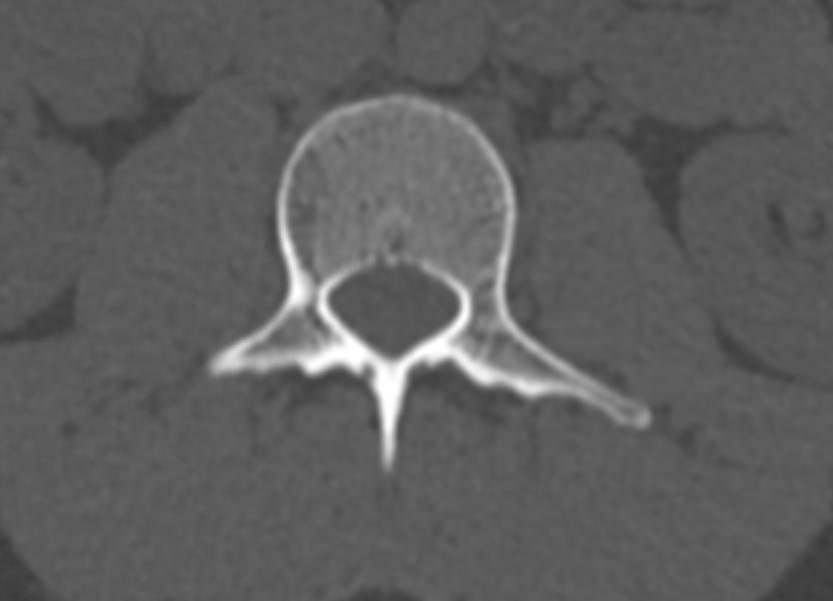

Мультиспиральная компьютерная томография является одним из наиболее информативных методов диагностики дегенеративно-дистрофических заболеваний, травматических, воспалительных изменений, а также опухолевых процессов позвоночника. Методика предусматривает использование рентгеновского излучения для получения детализированных снимков костных структур позвоночника, межпозвонковых суставов и межпозвоночных дисков.

В клинике «Доступная медицина» установлены современные мультиспиральные компьютерные томографы экспертного класса TOSHIBA AQUILION в различных модификациях (64-срезовый и 128-срезовый), на которых выполняются комплексные обследования позвоночника, включая одномоментное исследование несколько отделов. Аппараты производят сканирование с помощью рентгеновских лучей, делая тончайшие срезы с шагом от 0,5 мм, затем с помощью компьютерных программ полученные данные преобразуются в изображения трехмерного формата, что обеспечивает точность и достоверность диагностики.

С помощью мультиспиральной КТ можно диагностировать:

- травматические повреждения позвоночника (компрессионные и оскольчатые переломы);

- стеноз (сужение) позвоночного канала;

- грыжи межпозвонковых дисков (протрузии, экструзии и грыжи Шморля);